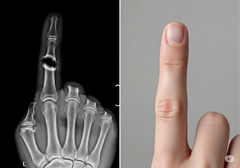

A Bone Biologics megközelítése a NELL-1 fehérjére összpontosít, egy olyan növekedési faktorra, amely természetes módon részt vesz a csontfejlődésben. Preklinikai vizsgálatok kimutatták, hogy a NELL-1 egyedülálló módon képes arra, hogy pontosan ott serkentse a robusztus csontnövekedést, ahol arra szükség van, miközben egyidejűleg gátolja a zsírsejtek képződését, ami más biológikumok esetében gyakori probléma. Ez a célzott hatás megbízhatóbb fúziókat és kevesebb szövődményt eredményezhet.

A vállalat jelenleg kísérleti klinikai vizsgálatot végez Ausztráliában a NELL-1 alapú csontátültetési eszközével degeneratív porckorongbetegségben szenvedő betegek számára. Az Egyesült Államokban a szabadalmi oltalom biztosítása kritikus része a stratégiának, mivel a vállalat a klinikai programjának előrehaladásán és végül az FDA jóváhagyásának megszerzésén dolgozik. A szabadalmi bejelentés híre jelentős emelkedést okozott a vállalat részvényeinek árfolyamában, ami a befektetők optimizmusát tükrözi a technológia azon lehetőségével kapcsolatban, hogy megzavarhatja a gerincimplantátumok piacát.